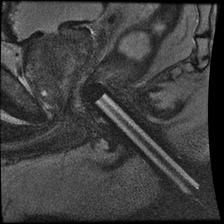

vermafigure-1aresize

Figure 1 is a 48 year old male with a PSA of 5.23 ng/ml and biopsy proven prostate carcinoma of Gleason score 10 (5.5).